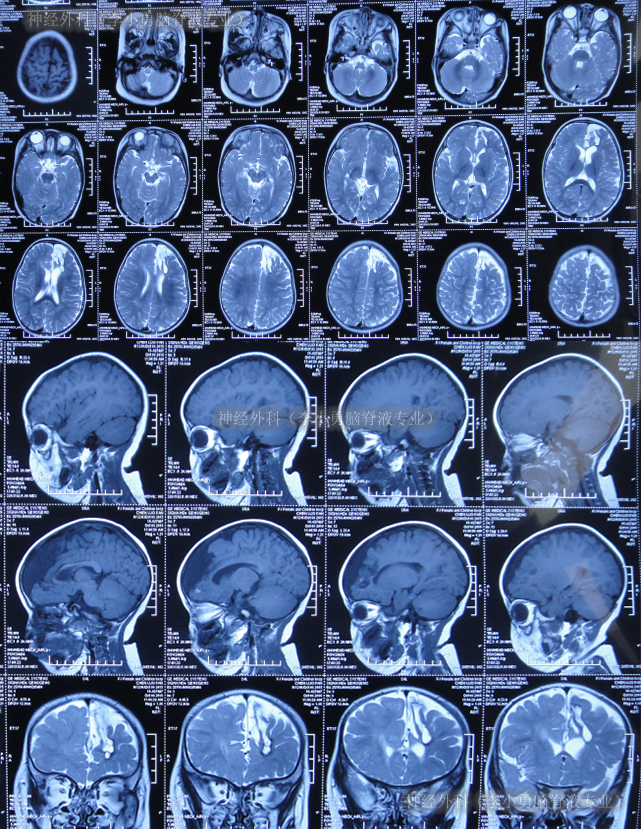

二、神经外科(李小勇脑脊液专业)治疗过程和结果

2017年7月20日(癫痫灶切除术后86天即脑室腹腔分流管脑室端探查术后3天,又即脑室腹腔分流术后30天),入院时:高热39.2度,时常哭闹,头围大至55厘米(1岁婴儿头围正常范围为42.6cm-50.5cm),理解力低于同龄人。左侧额颞顶可见一弧形手术切口疤痕,切口缝线仍未拆除;左额可见一长约3cm纵行手术切口疤痕,愈合不良,相应头皮水肿明显;左侧前胸壁引流管走行区可见皮肤隆起;腹部稍膨隆(图-15)。

图-15:2017年7月20日入院时

入院时头颅CT示癫痫术后,左侧额顶骨术后改变,左侧侧脑室引流术后状态,幕上脑室系统扩,多处硬膜下积液、部分见积气(图-16)。

图-16:2017年7月20日头颅CT

入院当天拔除了原脑室腹腔分流管+侧脑室外引流术。术后次日引流出黄色的脑脊液(图-17)。

图-17:2017年7月21日

入院5天即2017年7月24日,体温由入院时连续高热39.2度降至37.2度,情绪变稳定(图-18);原分流管脑室端细菌回报为表皮葡萄球菌。

图-18:2017年7月24日

入院7天即2017年7月26日,体温变得正常,查头颅CT示脑室外引流术后状态(图-19)。

图-19:2017年7月26日头颅CT

入院12天即2017年7月31日,进行了右侧侧脑室腹部外引流术,术前术后头颅CT对比(图-20)。

图-20:2017年7月31日术前术后头颅CT

继续治疗1月的时间,期间患儿身体状态变得越来越好,情绪愉悦,肢体活动正常,期间2次查头颅CT均示脑室进一步缩小(图-21)。

图-21:2017年8月3日